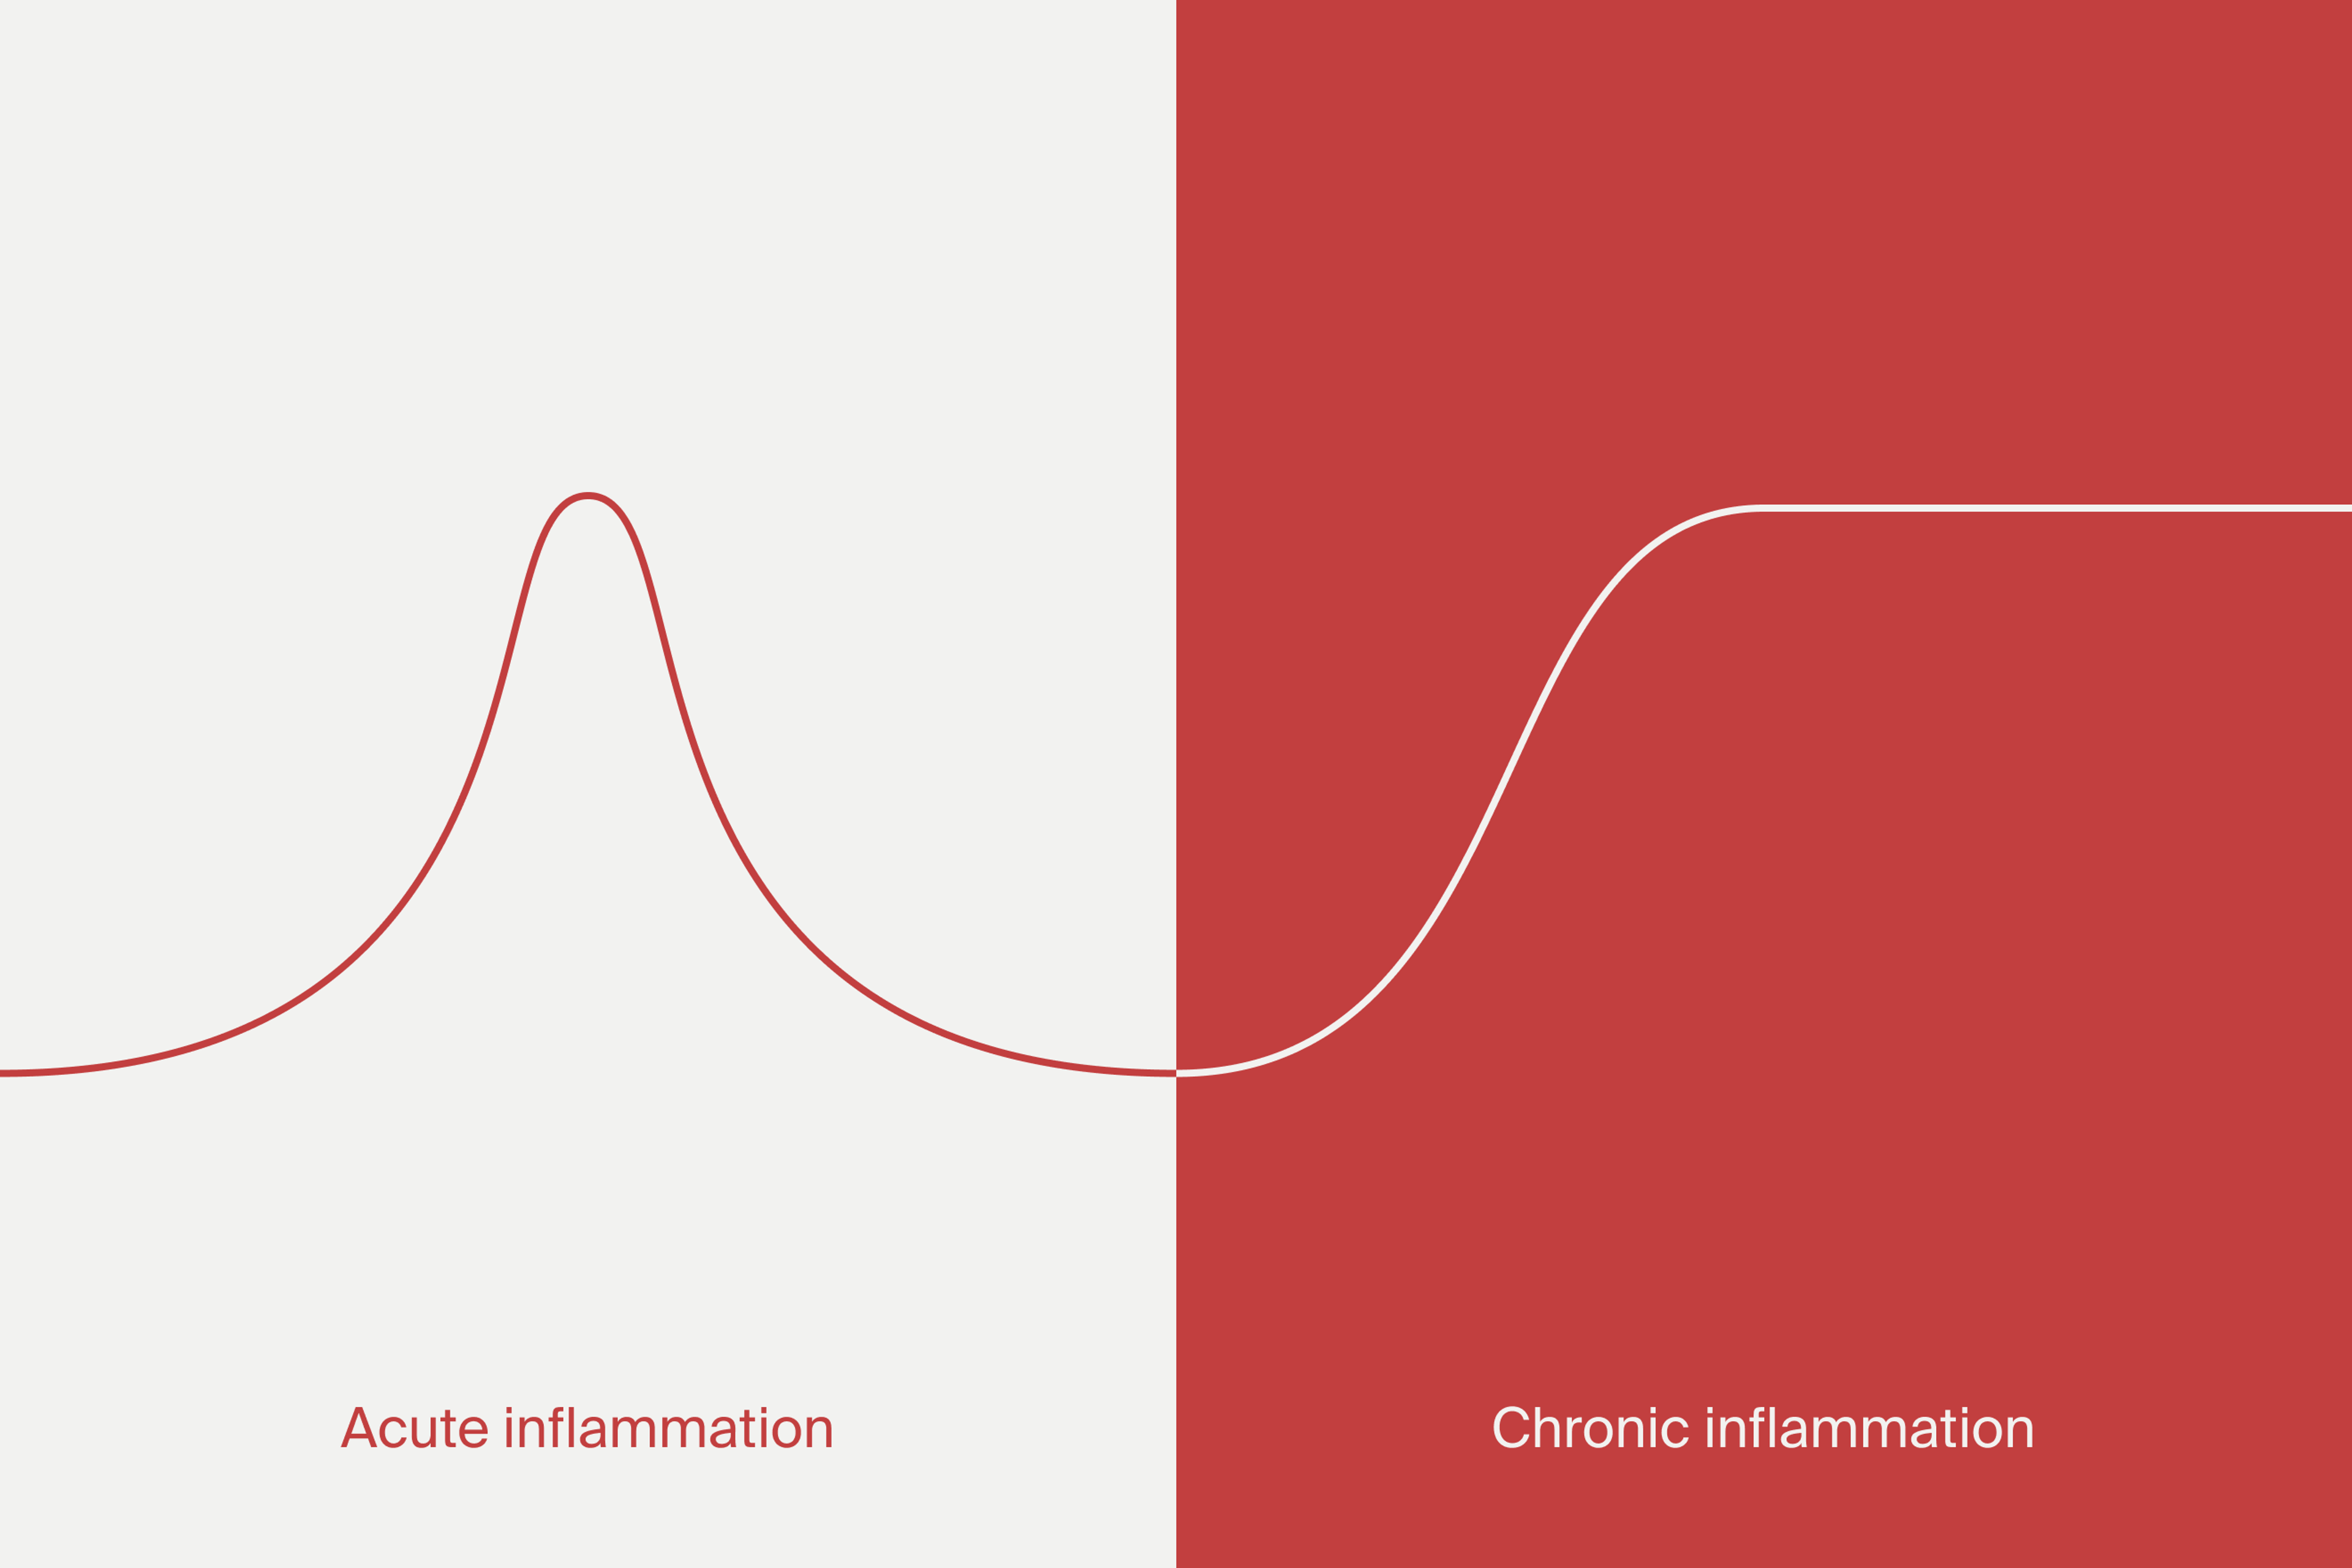

Acute vs. chronic inflammation

Let’s take a look at the different types of inflammation that occur in the body - acute and chronic inflammation.

Acute inflammation is our body’s natural response to illness and injury, where proteins and white blood cells are triggered as a response to a sudden event like cutting your finger. In this case, it is a necessary part of the healing process.

Chronic inflammation is when your body activates a similar immune response as it would in an acute event, but there is no injury or infection present. The inability of acute inflammation to appropriately resolve can also play a role in the development of chronic inflammation.

Chronic inflammation occurs over time and can be associated with inflammatory conditions like lupus, arthritis, Crohn’s disease, or colitis. It also can increase the risk of chronic diseases like heart disease, diabetes, or Alzheimer’s.[2]